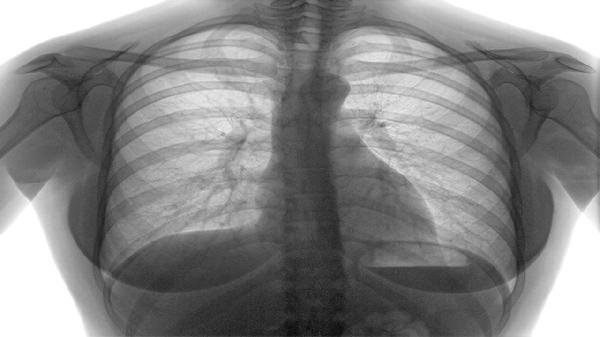

靶向治疗或免疫治疗起效时,机体营养吸收功能改善可能使食欲回升。这种积极变化通常伴随肿瘤标志物下降、影像学缓解等客观指标,但仍需定期监测营养状况。